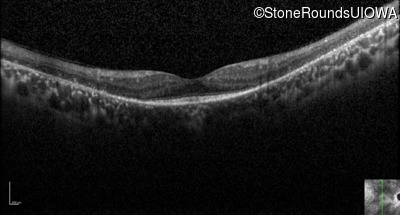

Optical Coherence Tomography - Left - 20/70 +1

Exemplar / OCT Stack